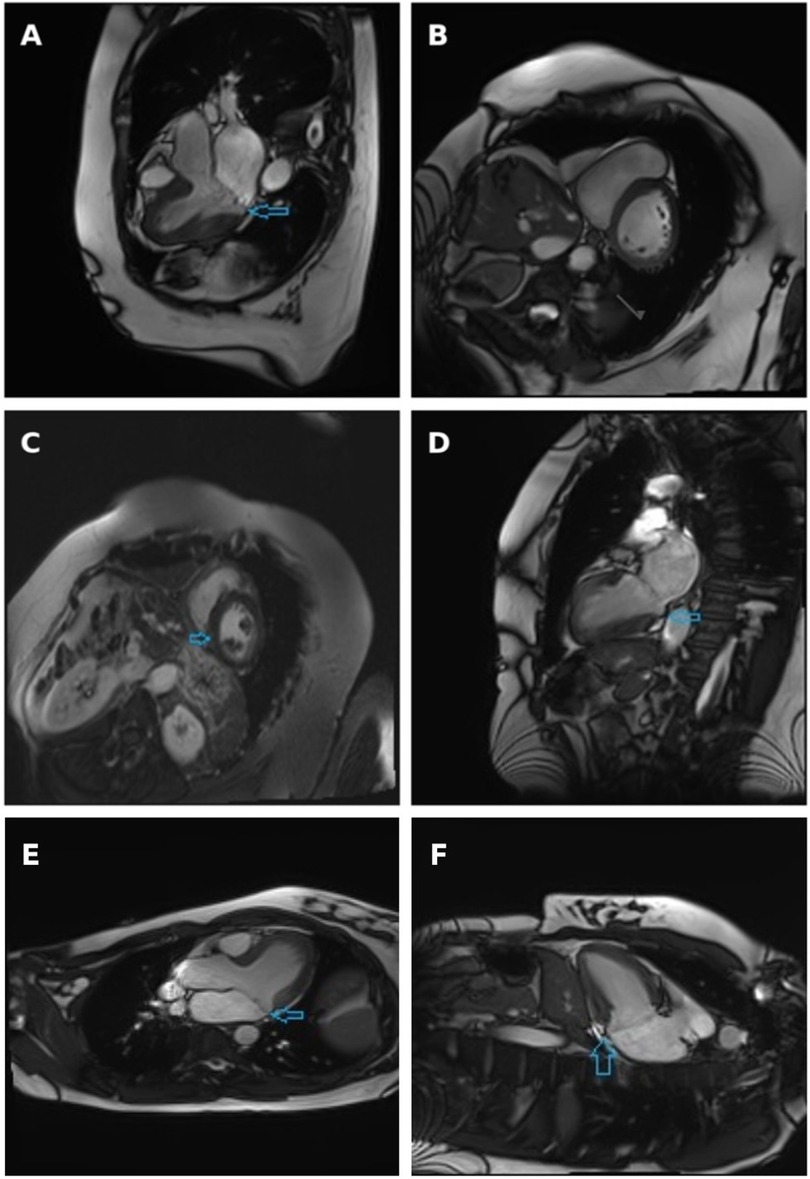

A comprehensive TTE revealed a thickened intraventricular septum, anterior MV leaflet prolapse, myxomatous degeneration of the MV leaflets, moderate to severe MVR with two eccentric jets, as well as LA and mitral annulus dilatation. Coronary artery angiography revealed mild non-obstructive coronary artery disease. CMR revealed inferior right ventricular insertion point fibrosis, moderate to severe MVR and MAD, all of which can be seen in Figure 2. Although LGE was detected, its distribution was located at the right ventricular insertion point, a site where enhancement is often considered non-specific and not necessarily indicative of a malignant arrhythmogenic substrate. Such findings, if isolated, should therefore be interpreted with caution, particularly in the absence of additional high-risk imaging features. However, additional Holter monitoring in this patient revealed polymorphic PVCs, several episodes of bigeminy, trigeminy and couplets. The PVCs exhibited both LBBB and right bundle branch block (RBBB) morphologies, suggesting multiple ectopic foci, most likely originating from the papillary muscles and/or adjacent inferior-basal LV myocardium. Moreover, a 12-lead ECG showed deep T-wave inversions in the inferior and lateral leads, which further supported the arrhythmogenic substrate and higher risk profile for this patient. The patient was discharged with a recommended adjustment of beta-blocker therapy and a plan for continued outpatient monitoring. A follow-up visit to a cardiologist was scheduled after 6 months, with 48 h HM and TTE assessment to be performed.

Figure 2

Cine three-chamber long-axis view (A), short-axis view at basal segments level (B) and two-chamber view (D) obtained at systole, with arrows indicating the separation between the posterior mitral valve leaflet insertion and the left ventricular myocardium. Late gadolinium enhancement short-axis view: arrow indicates non-specific fibrosis at the inferior right ventricular insertion point (C) Cardiac magnetic resonance imaging demonstrating mitral annular disjunction. Three-chamber long-axis view and (E) two-chamber view (F) obtained at end-systole, with arrows indicating the separation between the posterior mitral valve leaflet insertion point and the left ventricular myocardium.

MAD is best visualized in the TTE PLAX view and is often accompanied by myxomatous damage of MV leaflets. However, the most reliable and accurate tool used for the evaluation of fibrosis of myocardium and detection of MAD is CMR, as demonstrated in Figure 2. In a systematic literature review conducted by Drescher and colleagues, the diagnostic sensitivity of TTE and CMR was compared in the detection of MAD. MAD was detected in 17.3% of individuals using TTE, whereas the prevalence of MAD increased to 42.0% when the same individuals were assessed using CMR (13). To fully assess the extent of MAD, six LV long-axis cine sequences with 30° interslice rotation must be acquired around the mitral annulus, evaluating its' circumferential extent and maximal width of the disjunction (14). Another advantage of CMR compared to TTE is the ability to evaluate focal fibrosis of myocardium using LGE as well as diffuse LV fibrosis, which is associated with an increased risk of VAs, determined by T1 mapping (15). In presence of MAD, fibrosis is usually located close to the mitral annulus in the basal LV wall, including papillary muscles and inferior LV wall. Another common finding in patients with MAD is tricuspid annular disjunction (TAD), which, according to a study by Aabel et al., has been reported to occur in approximately 50% of examined MAD cases. The coexistence of TAD and MAD suggests a broader involvement of the atrioventricular junction rather than an isolated MV pathology and has been associated with a greater increase in the arrhythmic risk. Although standard CMR protocols can visualize the tricuspid annulus, TAD still often remains underdiagnosed (16). However, in the two cases presented in this study, no evidence of concomitant TAD was found on CMR.